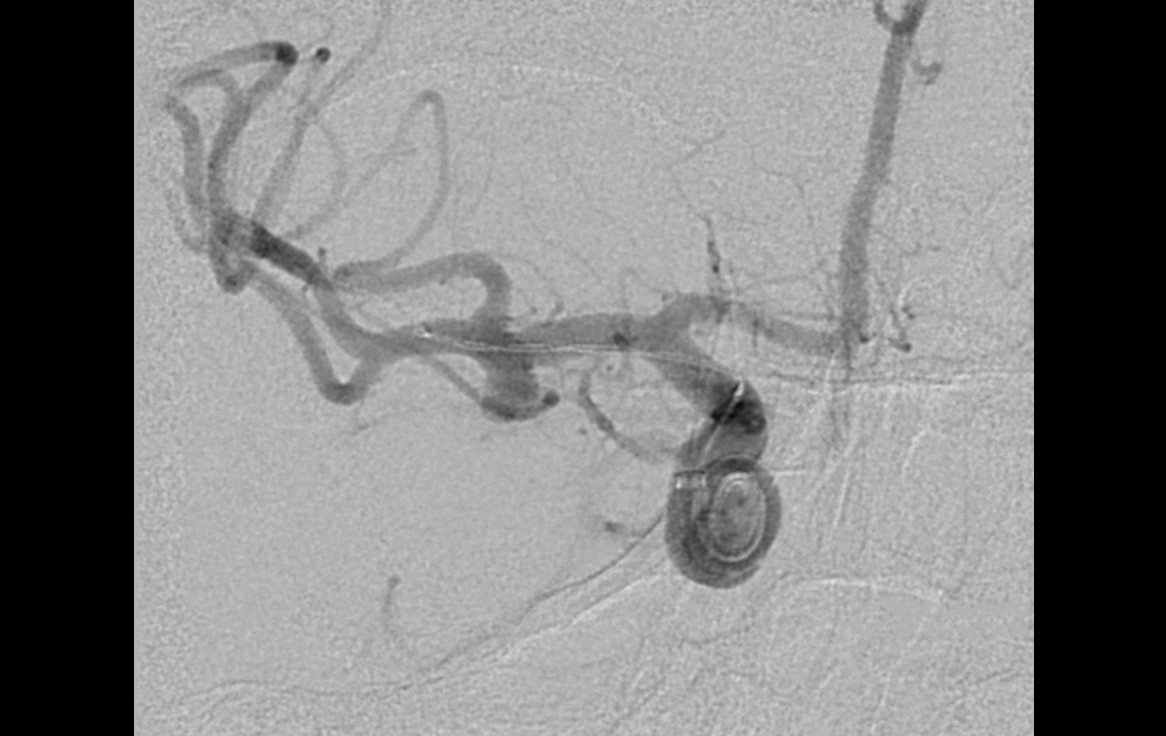

Aneurisma incidental relacionado a artéria cerebral média diagnosticado após investigação de cefaleia. Realizado tentativa de embolização com micromolas sem sucesso, sendo optado pelo tratamendo endovascular com stent redirecionador de fluxo Fred Jr 03 x 14 x 19 mm.